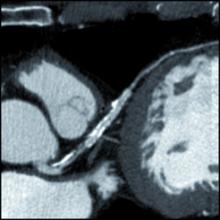

There has been growing clinical evidence to show computed tomography (CT) coronary artery calcium scoring shows a close correlation with a person’s long-term risk for heart disease. This data convinced the American College of Cardiology (ACC) to include CT calcium scoring in its revised guidelines for prevention and cholesterol released last fall. In addition, the ACC highlighted the evidence for CT calcium scoring as a late breaking session at its 63rd Annual Scientific Session in March.